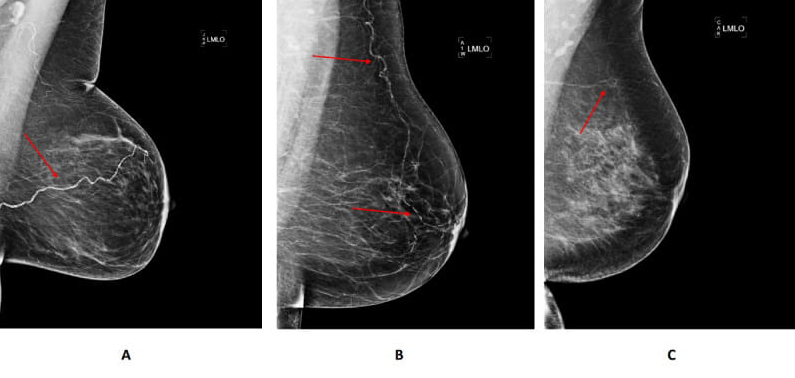

On a mammogram, BAC appears as thin, white lines tracing the path of breast arteries. These calcium streaks form in the middle layer of the artery wall, where they cause stiffness rather than blockage. Unlike plaque that clogs arteries, this type of calcification makes them less flexible.

*Examples of BAC (A = severe, B = moderate, C = light). Image source: American Heart Association, Circulation: Cardiovascular Imaging (2022).